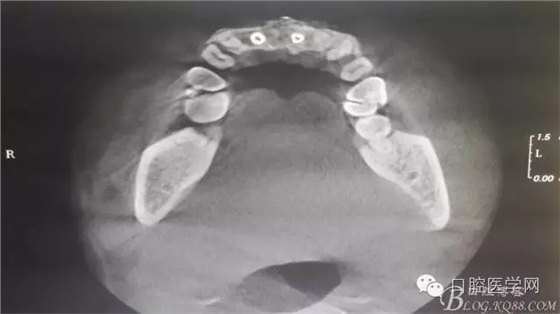

半年后...

遺憾沒有保留術(shù)前口內(nèi)照片,只有術(shù)后的。

后期的修復(fù)工作由之前的轉(zhuǎn)診醫(yī)生后續(xù)處理,由于GBR過程骨膜減張導(dǎo)致角化牙齦不足3mm,建議角化牙齦移植改變其更好的牙齦生物型。